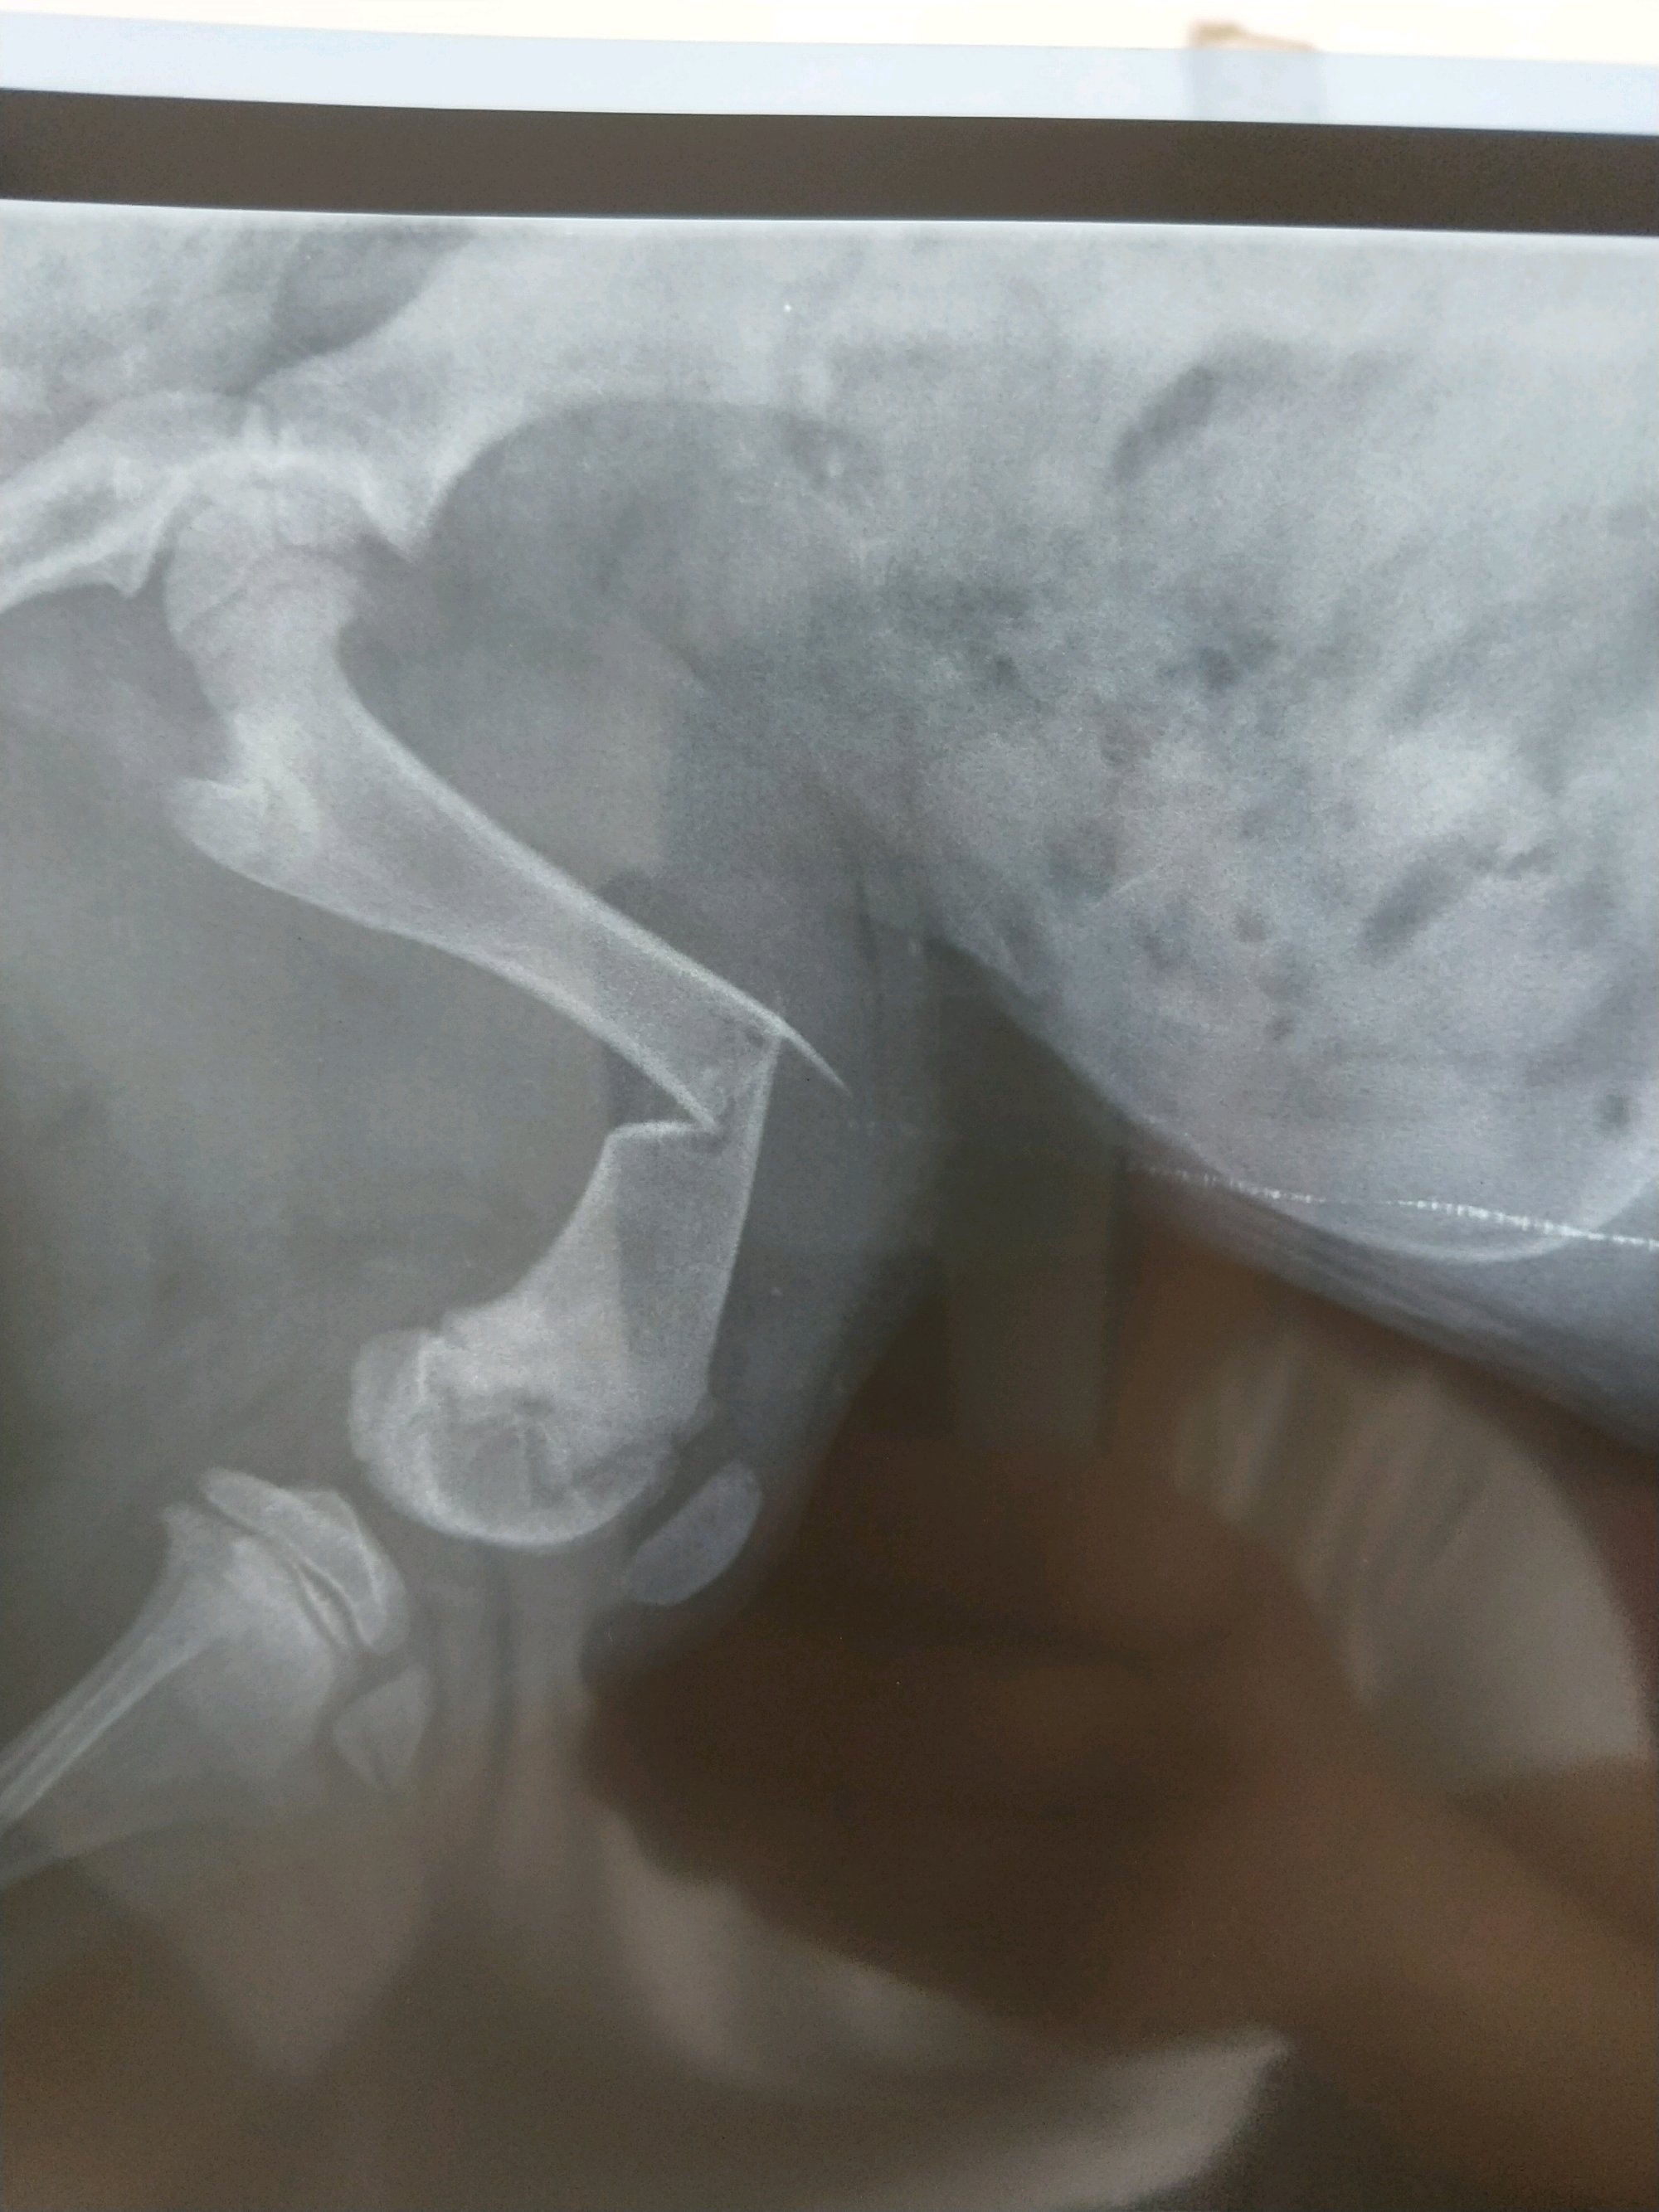

求问各位吧友,家里傻狗5个月,前天回家发现狗子后腿外翘,不能着地,疼的一直流口水。怪心疼的。

带去医院拍片,医生说断了骨头,问我外固定还是内固定。可是外固定他说位置太尴尬,钢钉没地方打。内固定不牢靠,一动就等于白弄。两肿固定都是一半的几率残废。

但是看来看去不知道哪里骨折了。医生自己还把图发群里问别人。求各位吧友帮忙看看

狗子今天精神就特别好,还能扒笼子,让他别蹦但就是静不下来。看别人家狗子骨折都是好几天没法动弹的。所以到底骨折没有哦?